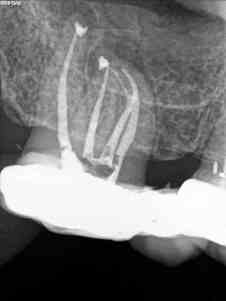

C) Por último, no encontramos un 1.6 con otra pulpitis irreversible.

C)